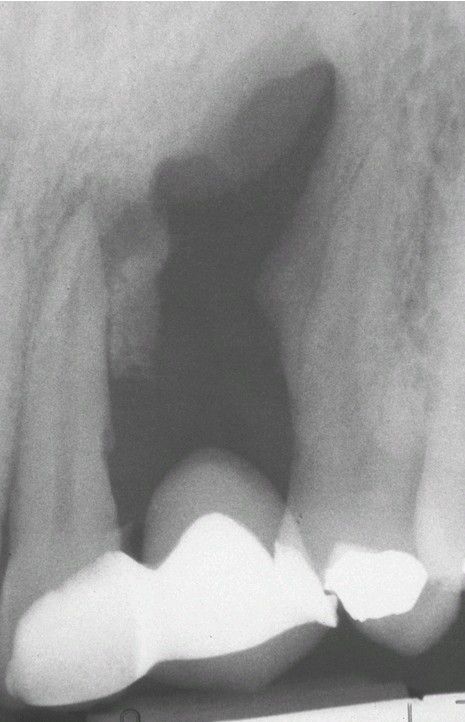

Periapical Fibrous Scar.

Periapical radiolucency of maxilla at the previous site of extraction in which both cortical plates were lost. The site was filled with dense collagenous tissue.